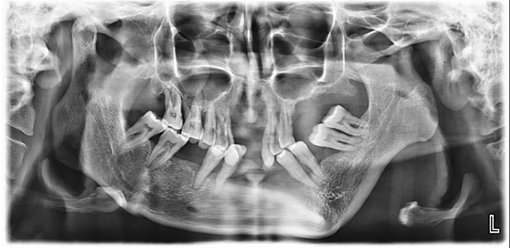

On investigation, an orthopantomogram (OPG) was advised. The radiograph reveals significant asymmetry of the mandible, with notable hypoplasia of the left condyle and a marked reduction in the vertical height of the left ramus. The left antegoinial notch appears prominently accentuated, suggesting altered mandibular growth. Despite these morphological changes, the cortical bone appears well-defined, with normal bone density and an intact lower border of the mandible. The glenoid fossa on the left side maintains a normal appearance, without evidence of dysplasia or displacement. In contrast, the right side of the mandible appears structurally normal (Figure 4).

Figure 4 Orthopantomogram showing mandibular asymmetry with hypoplastic left condyle, reduced vertical height of the left ramus, and a prominent antegonial notch. Cortical bone and mandibular border are intact with normal bone density. The left glenoid fossa appears normal; the right mandible is structurally unremarkable.

Radiographic limbs show bony ankylosis of the elbow joint, with associated hypoplasia of the ulna and proximal radius, leading to elbow flexion deformity on the left side (Figure 5). Chest x-rays show no apparent abnormalities: normal lung fields, cardiac silhouette, and bony structures (Figure 6) PA skull view show hypoplastic maxilla, prominent antigoinial notch and deviation of mandible to left side (Figure 7 &Table 1).

Radiographic imaging further supports the diagnosis. The orthopantomogram (OPG) reveals mandibular asymmetry, left-sided condylar hypoplasia, and a reduction in vertical ramus height, all of which are indicative of the mandibular underdevelopment typical of Nager syndrome.10 The prominent antegonial notch also points to abnormal mandibular growth, a finding frequently reported in these patients.17 Despite these skeletal changes, the well-defined cortical bone suggests that severe osteodysplastic conditions are unlikely.